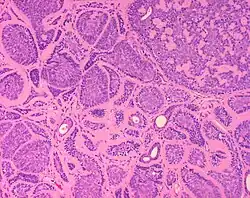

Micrograph of a dermal cylindroma in H&E stain.

Micrograph of a dermal cylindroma in H&E stain. -

Dermal cylindroma. Puzzle-like distribution of tumour foci.